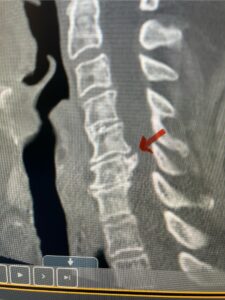

The next patient is a 54 year-old male who presents with 3 years of neck pain with associated numbness and tingling of his extremities. Patient had had physical therapy, chiropractic care, and epidural steroid injections with no significant relief. The patient on exam had weakness in a long tract distribution on the left. MRI revealed four level disc disease from C3-4 to C6-7 with a moderate kyphosis and cord compression and signal change at C3-4 (Fig. 9). Because of the kyphotic deformity it was decided to perform a four-level anterior cervical discectomy and interbody cage at each segment as well as plate. The patient had significant osteophyte disease at each level which required a high-speed drill to shave down the osteophytic disease and remove and decompress the foramina with fine Kerrison. Intraoperative imaging revealed good placement of the cages and plate at each level (Fig. 10). The patient had good relief of his preoperative symptoms.

Fig. 9a Sagittal T2-weighted cervical MRI demonstrating severe upper cervical spinal cord compression secondary to C2 anterior subluxation on C3 with development of thickened posterior degenerative material (red arrow)

Fig. 9b

Fig. 9c